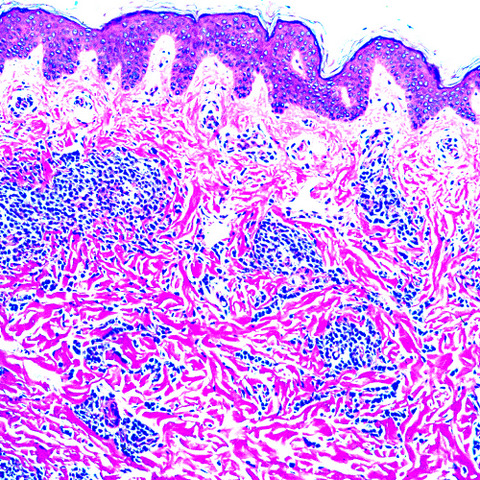

Microscopic (histologic) description

- Within the macules and plaque, mast cells are predominantly in papillary dermis

- Mast cells are round or spindle shaped with abundant eosinophilic cytoplasm, distinct cytoplasmic boundaries, large pale nuclei

- Eosinophils are often present

- Also edema of papillary dermis, subepidermal vesiculation

- In telangiectasia macularis eruptive perstans, features may be subtle, with increased mast cells around dilated superficial capillaries, basal cell hyperpigmentation of overlying epidermis, superficial lymphohistiocytic infiltrate

Microscopic (histologic) images